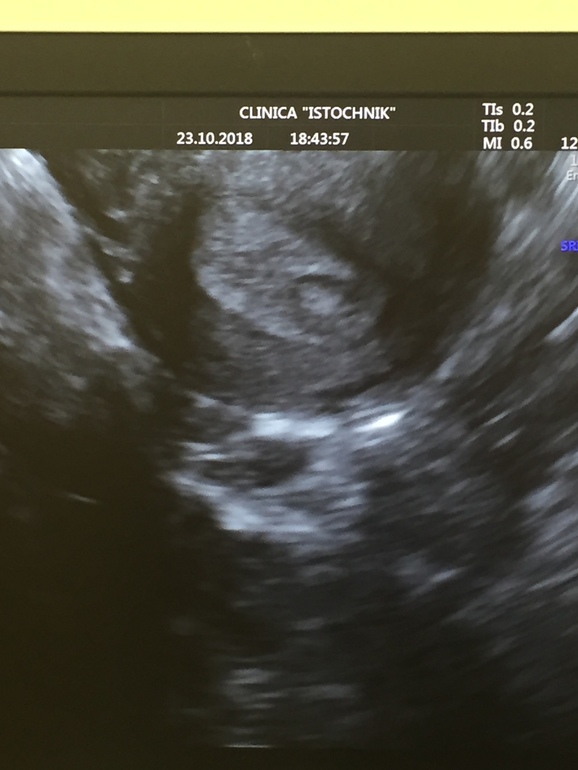

И вот сегодняшнее УЗИ:

В центре округлое образование это аномальное ПЯ.

Начиталась про ложное ПЯ, теперь снова в панике. Вдруг оно как раз ложное? Но бывает ли ложное ПЯ таких размеров? Вроде как оно выросло с ВС с 3,8 до 6,5 мм, да и место расположения совпадает.